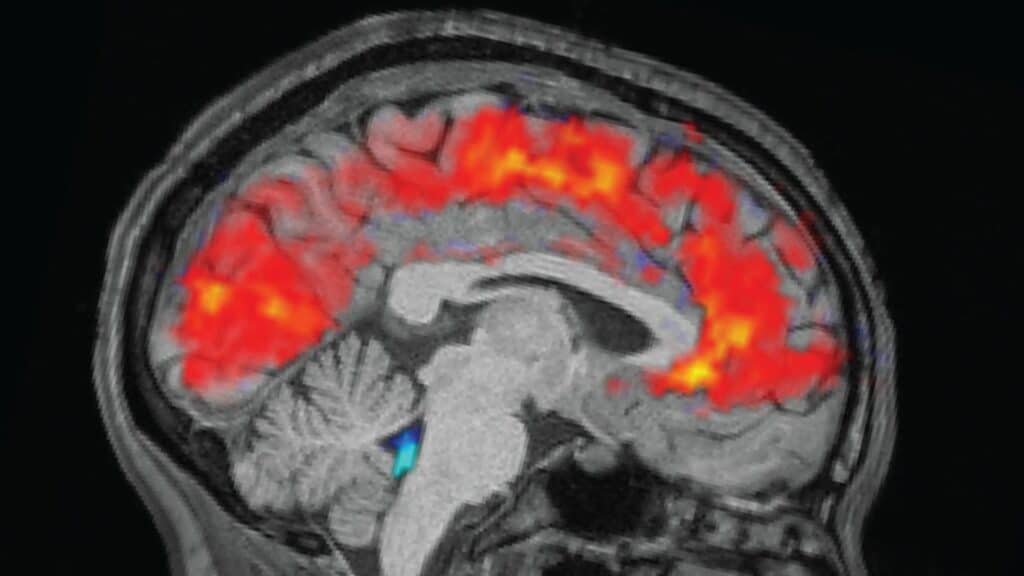

Study Finds 40% of Fmri Brain Scans Misread Neural Activity

A groundbreaking study reveals that functional magnetic resonance imaging (fMRI), a cornerstone of modern brain research, misinterprets neural activity in about 40% of cases. Researchers from the Technical University of Munich (TUM) and Friedrich-Alexander-University Erlangen-Nuremberg (FAU) discovered that increased fMRI signals often correspond to reduced brain activity, upending a key assumption behind tens of thousands […]